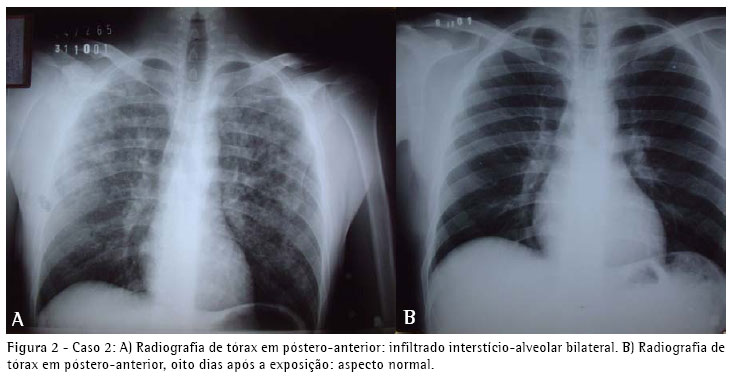

A radiografia simples do tórax, na admissão, mostrava infiltrado interstício-alveolar difuso (Figura 1). A gasometria com oxigênio por máscara facial a 8 l/min apresentou pH de 7,40, pressão arterial de oxigênio de 65 mmHg, pressão arterial de gás carbônico de 40 mmHg e saturação arterial de oxigênio de 92%. O teste rápido para o vírus da imunodeficiência humana foi negativo.

O quadro clínico e radiológico dos três pacientes foi compatível com edema pulmonar e insuficiência respiratória aguda. A evolução revelou-se favorável e no seguimento clínico, radiológico (Figuras 1, 2 e 3) e de função pulmonar por dezoito meses não apresentaram nenhuma repercussão respiratória.

O quadro clínico e radiológico dos três pacientes foi compatível com edema pulmonar e insuficiência respiratória aguda. A evolução revelou-se favorável e no seguimento clínico, radiológico e de função pulmonar por dezoito meses, não apresentaram nenhuma repercussão respiratória.